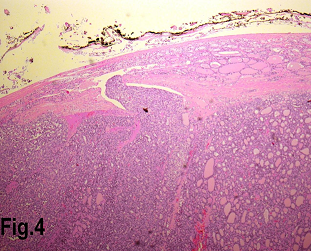

Figure 4.Low power view showing a follicular carcinoma with capsular invasion. (Hematoxylin & eosin, original magnification ×200).

Solitary benign adenomas were found in 23 cases, the peak frequency was fourth and fifth decade. Female accounted for 12 cases (70.5%) for follicular adenoma (Figure 2) and 3 cases (50%) for Hurthle cell adenoma. Thyroid malignancy and it was reported in 62 cases. Papillary carcinoma (Figure 3) was the most common type of thyroid malignancy found in 44 cases (71%) followed by follicular carcinoma (9.6%) (Figure 4), medullary carcinoma (1.6) and poorly differentiated carcinoma (1.6%) (Table 3). The peak incidence for patients with thyroid malignancy in this series was third decade and male to female ratio was 3.7:1.